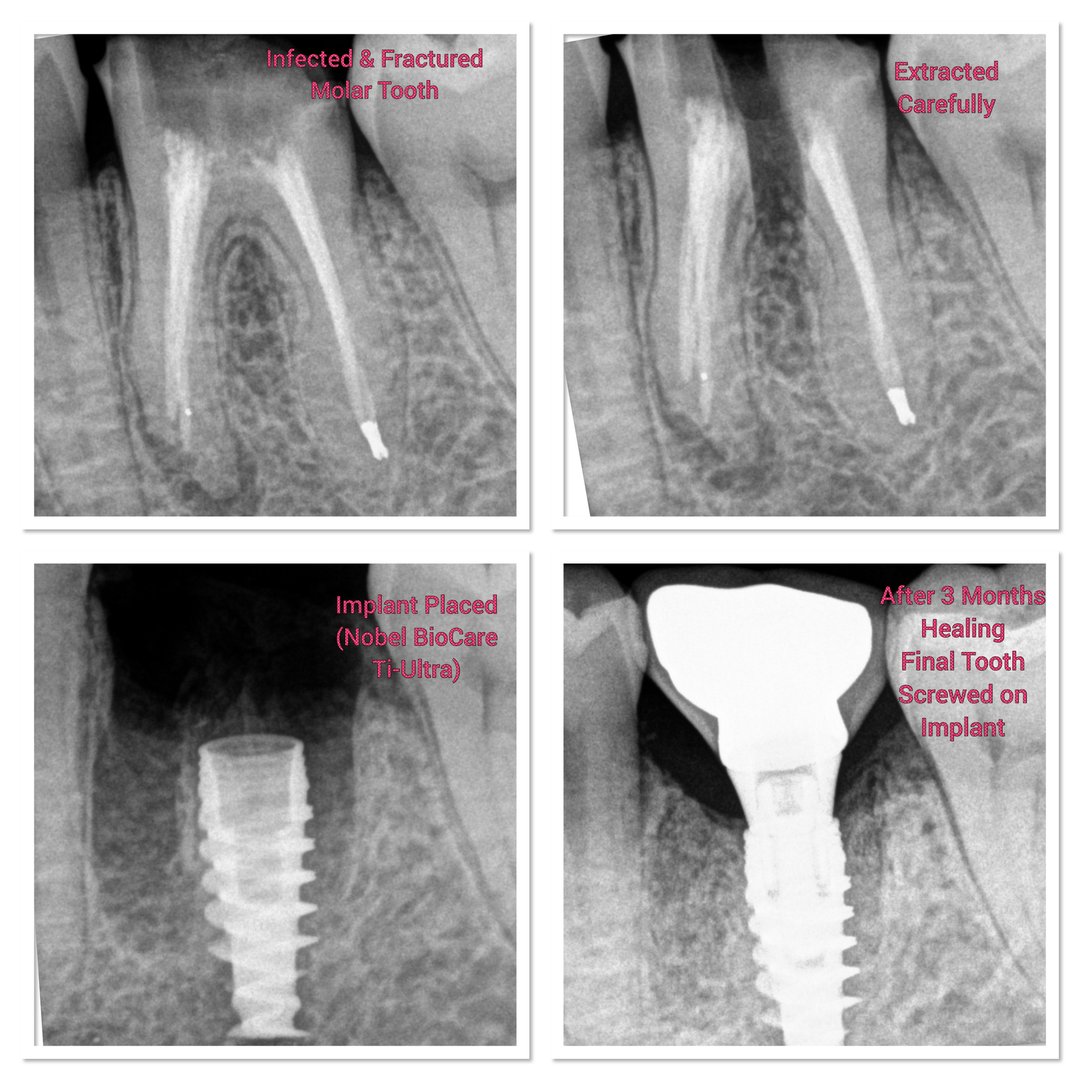

Burute Dental Clinic is the best dental clinic in Pimpri Chinchwad (PCMC) Pune, led by Dr. Mrunal Burute and Dr. Madhura Burute, expert implant dentists. We specialize in dental implants, full mouth dental implants, all-on-4, all-on-6, all-on-X implants, single tooth implants, immediate dental implants, and complex dental implant cases with high success rates. Known as a top dental implant clinic near me, we treat failed implants, severe bone loss, and advanced full mouth rehabilitation cases with precision. Our dental care services include root canal treatment, painless RCT, teeth whitening, aligners, braces, pediatric dental care, cosmetic dentistry, and complete oral care. If you are searching for dental implants near me visit us